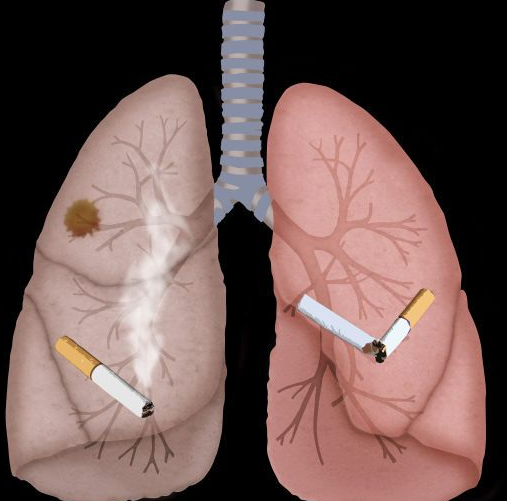

肺癌刚刚开始的时候都是咳嗽,与偶的人咳嗽的厉害的时候还会有咳血的症状,通常都是这个时候才会引起重视,到医院去检查的,而很多人都是拖到咳血,胸痛难忍吃药也比起多大的作用的时候才去医院检查的,到医院检查就是肺癌晚期。可能很多人想要知道肺癌晚期死前症状,我们一起来看一下。